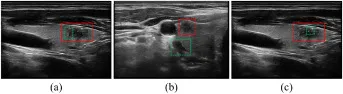

图1. 超声视频分割的挑战:(a) 模糊边界,(b) 混淆位置,© 散斑噪声,红色轮廓指甲状腺结节,绿色轮廓指混淆区域。